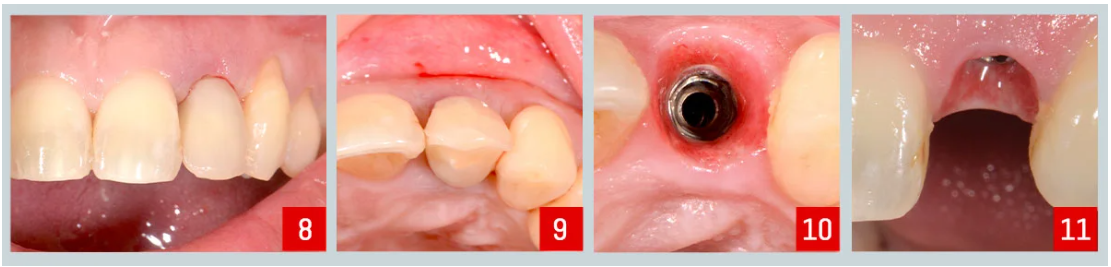

Resultado postoperatorio :

Las fotos muestran una cicatrización exitosa y una excelente estabilidad primaria (imágenes 8 y 9) .

Cuatro meses después :

Comenzó la fase restauradora. Los tejidos blandos se veían sanos y bien cicatrizados, sin complicaciones (imágenes 10 y 11) . En esta etapa, reemplazamos el pilar inicial con un pilar C-Tech OMNI, elegido por su perfil más estrecho que permite una mejor adaptación a los tejidos.